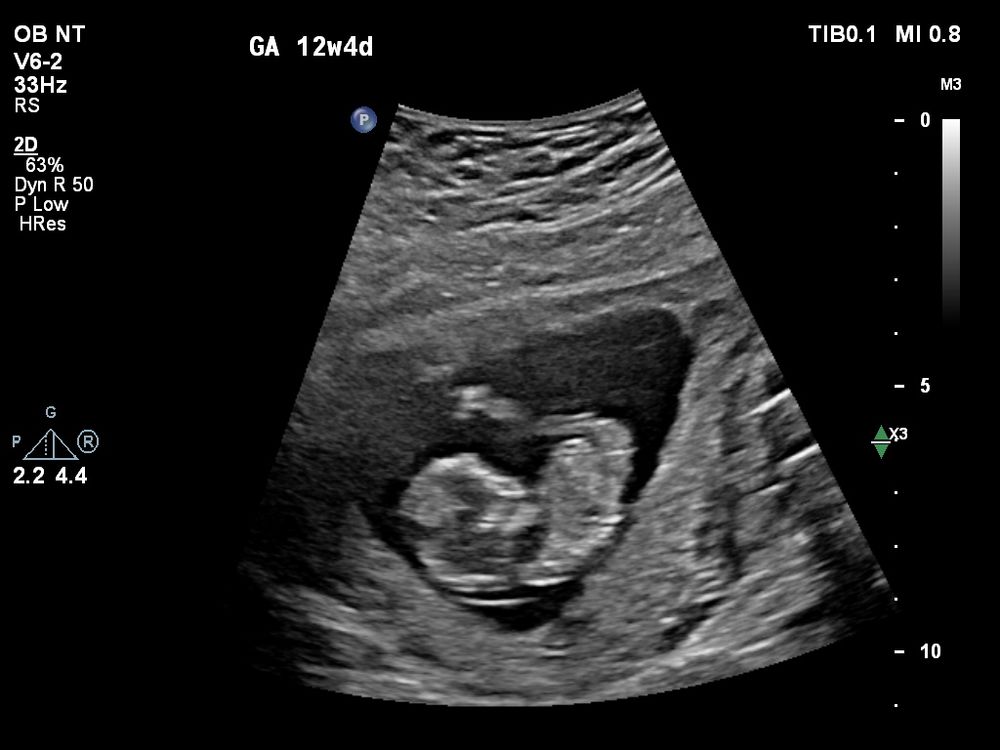

Сегодня сходили с молодым человеком на свидание с лялей 😊 Все у неё/него хорошо, показал(а) нам как плавает, ножки задирает (1 фото). Во время УЗИ мне показалось, что половой бугорок прямо смотрит, надеялась, что на видео/фотографиях все отмечено, а что-то как-то нет, наверное, не в настроении на фотографии был(а) 😀😅

По первым УЗИ (и по овуляции) сегодня срок 12+1, а по скринингу срок 12+5 (6.2см)😅